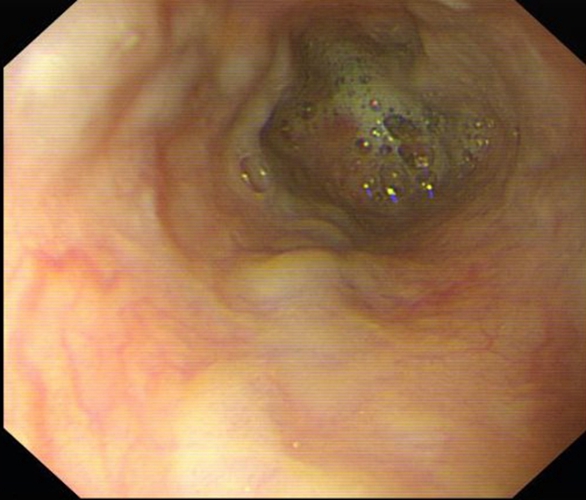

急性胃炎圖片

急性胃炎陽性表現

急性胃炎陽性的表現

急性胃炎

A:應激性潰瘍多是由於機體遭受了嚴重的創傷,感染或者休克等等而導致的,如果有重大疾病,還應注意適當的給予h2受體拮抗劑,儘早的開啟腸內營養,當機體重大疾病治療好轉後,這種情況也可恢復,所以並不需要過多的擔心。……

A:應激性潰瘍是在身體遭受重大疾病,比如休克,手術,全身感染,創傷等等,而導致的急性胃炎多伴有出血的急性胃粘膜病變,與長期應用阿司匹林,消炎痛或者類固醇激素治療也有相關性,但多是由於身體處於應激反應而造成的。……

A:機體處於應激狀態,就會導致應激性潰瘍的發生,比如嚴重的顱腦疾病,大面積燒傷,外傷,手術,或者休克,腎衰等等,再或者長期應用阿司匹林,消炎痛等都會導致胃粘膜損傷而出現應激性潰瘍。……